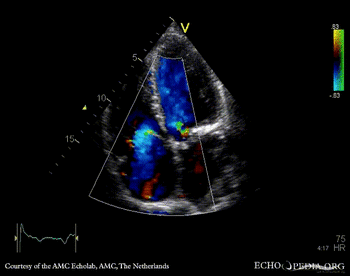

E00437.gif E00438.gif

A4CH: enlarged atria and ventricles A3CH: severe aortic and mitral regurgitation